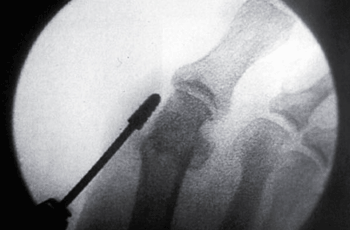

TÉCNICA QUIRURGICA